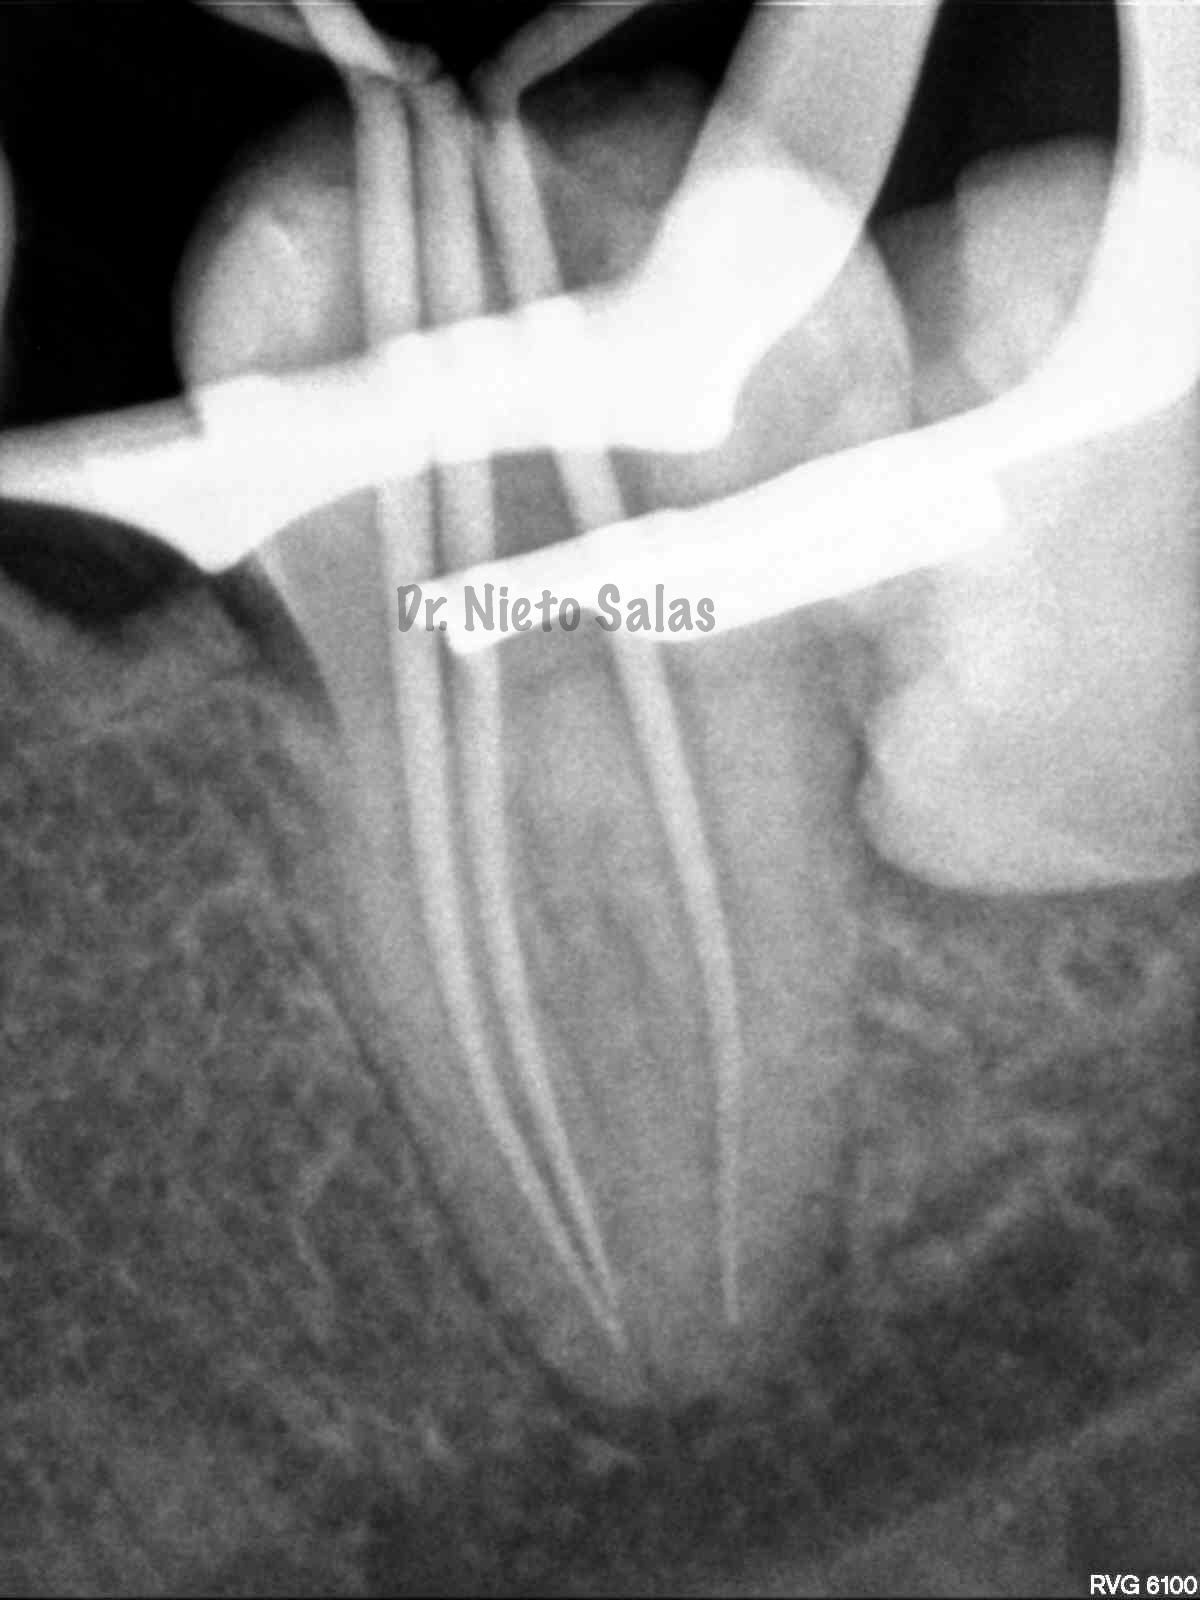

Intentamos mantener la permeabilidad y la forma de  los conductos. Instrumentamos con Pathfile y Mtwo hasta un 25-6%.

(ORTO)                                                               (DISTO)

(MESIO)